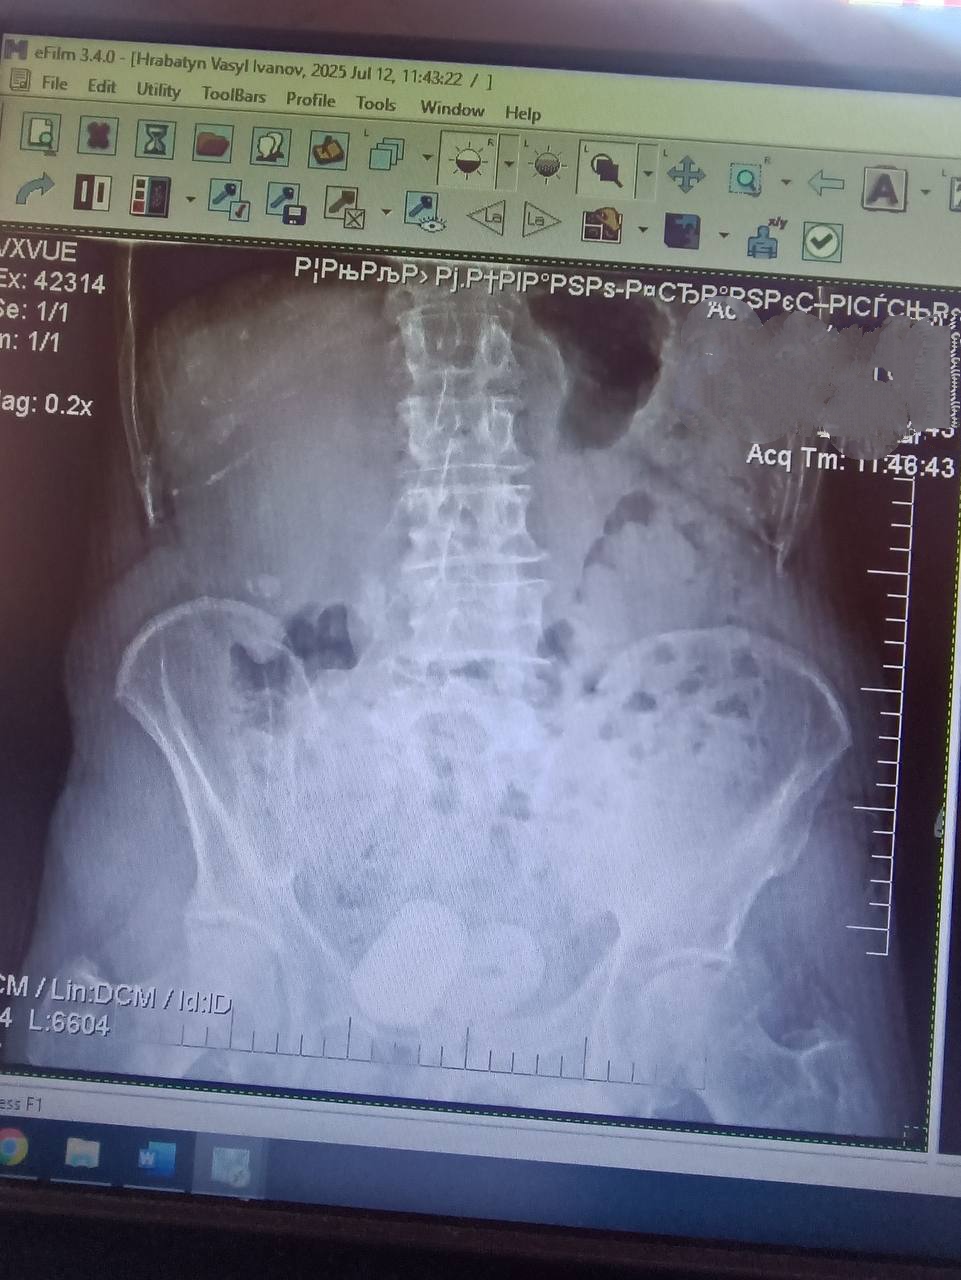

До урологів Центральної міської клінічної лікарні звернувся 76-річний мешканець Івано-Франківська зі скаргами на кров у сечі. Під час обстеження — УЗД та оглядової урографії — медики виявили два великі конкременти в сечовому міхурі, кожен розміром близько 4 см.

Через значні розміри каменів лікарі провели відкрите оперативне втручання — цистолітотомію. Операція виконувалася під спінальною анестезією через розріз над лобком.